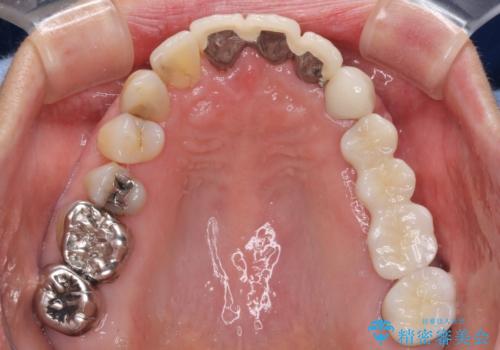

- 上の奥歯に装着されているブリッジが痛むとのことで来院された患者様です。

診察した結果、ブリッジの土台となっている歯が割れていたため、抜歯が必要となりました。

欠損している歯数が多いため、ブリッジによる補綴治療は困難と判断し、インプラントによる補綴治療を行うこととしました。